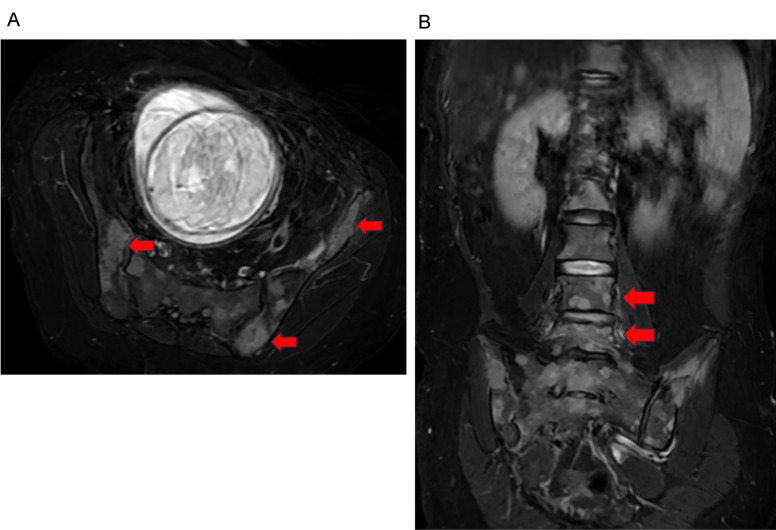

Case: A 41-year-old pregnant woman was admitted to our hospital because low back pain compromised her ability to stand. She was diagnosed with breast cancer-associated multiple bone metastases. Our unit was consulted for rehabilitation therapy, for which we formed a BMCB. The treatment was integrated and performed according to the recommendations of the BMCB. The patient underwent a cesarean section to initiate primary tumor treatment. After evaluating the risk of SREs, we provided her with rehabilitation therapy. Wearing a plastic molded thoracolumbosacral orthosis, she was able to walk with a pick-up walker. The patient continued outpatient chemotherapy and cared for her infant without experiencing any significant adverse events.

Abstract Image